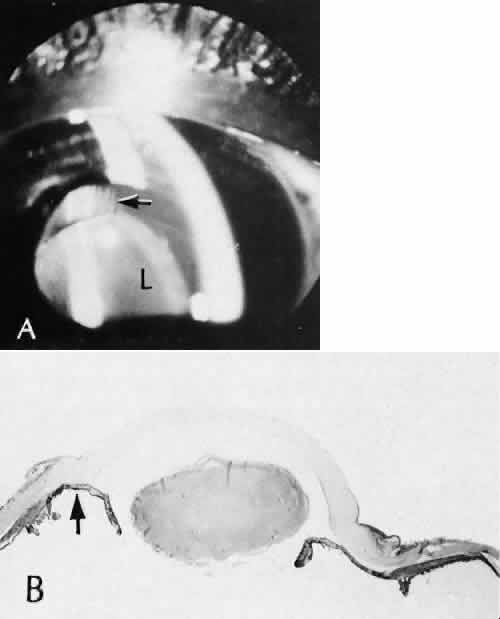

study of the evolution of retinal lesions in the rhesus monkey. American Journal of Ophthalmology 75(4):610–626, 1973. 44. Tso MO, Wallow IH, Elgin S: Experimental photocoagulation of the human retina. Archives of Ophthalmology 95(6):1035–1040, 1977. 45. Wallow IH, Tso MO, Elgin S: Experimental photocoagulation of the human retina. II. Electron microscopic

study. Archives of Ophthalmology 95(6):1041–1050, 1977. 46. Yoon YH, Marmor MF: Rapid enhancement of retinal adhesion by laser photocoagulation. Ophthalmology 95(10):1385–1388, 1988. 47. Miller B, et al: Effect of the vitreous on retinal wound-healing. Graefes Archive for Clinical & Experimental Ophthalmology 224(6):576–579, 1986. 48. Yamana T et al: The process of closure of experimental retinal holes in rabbit eyes. Gaefes Archive for Clinical & Experimental Ophthalmology 238(1):81–87, 2000. 49. Ozaki S et al: Influence of the sensory retina on healing of the rabbit retinal pigment

epithelium. Current Eye Research 16(4):349–358, 1997. 50. Perry DD, Reddick RL, Risco JM: Choroidal microvascular repair after argon laser photocoagulation. Ultrastructural